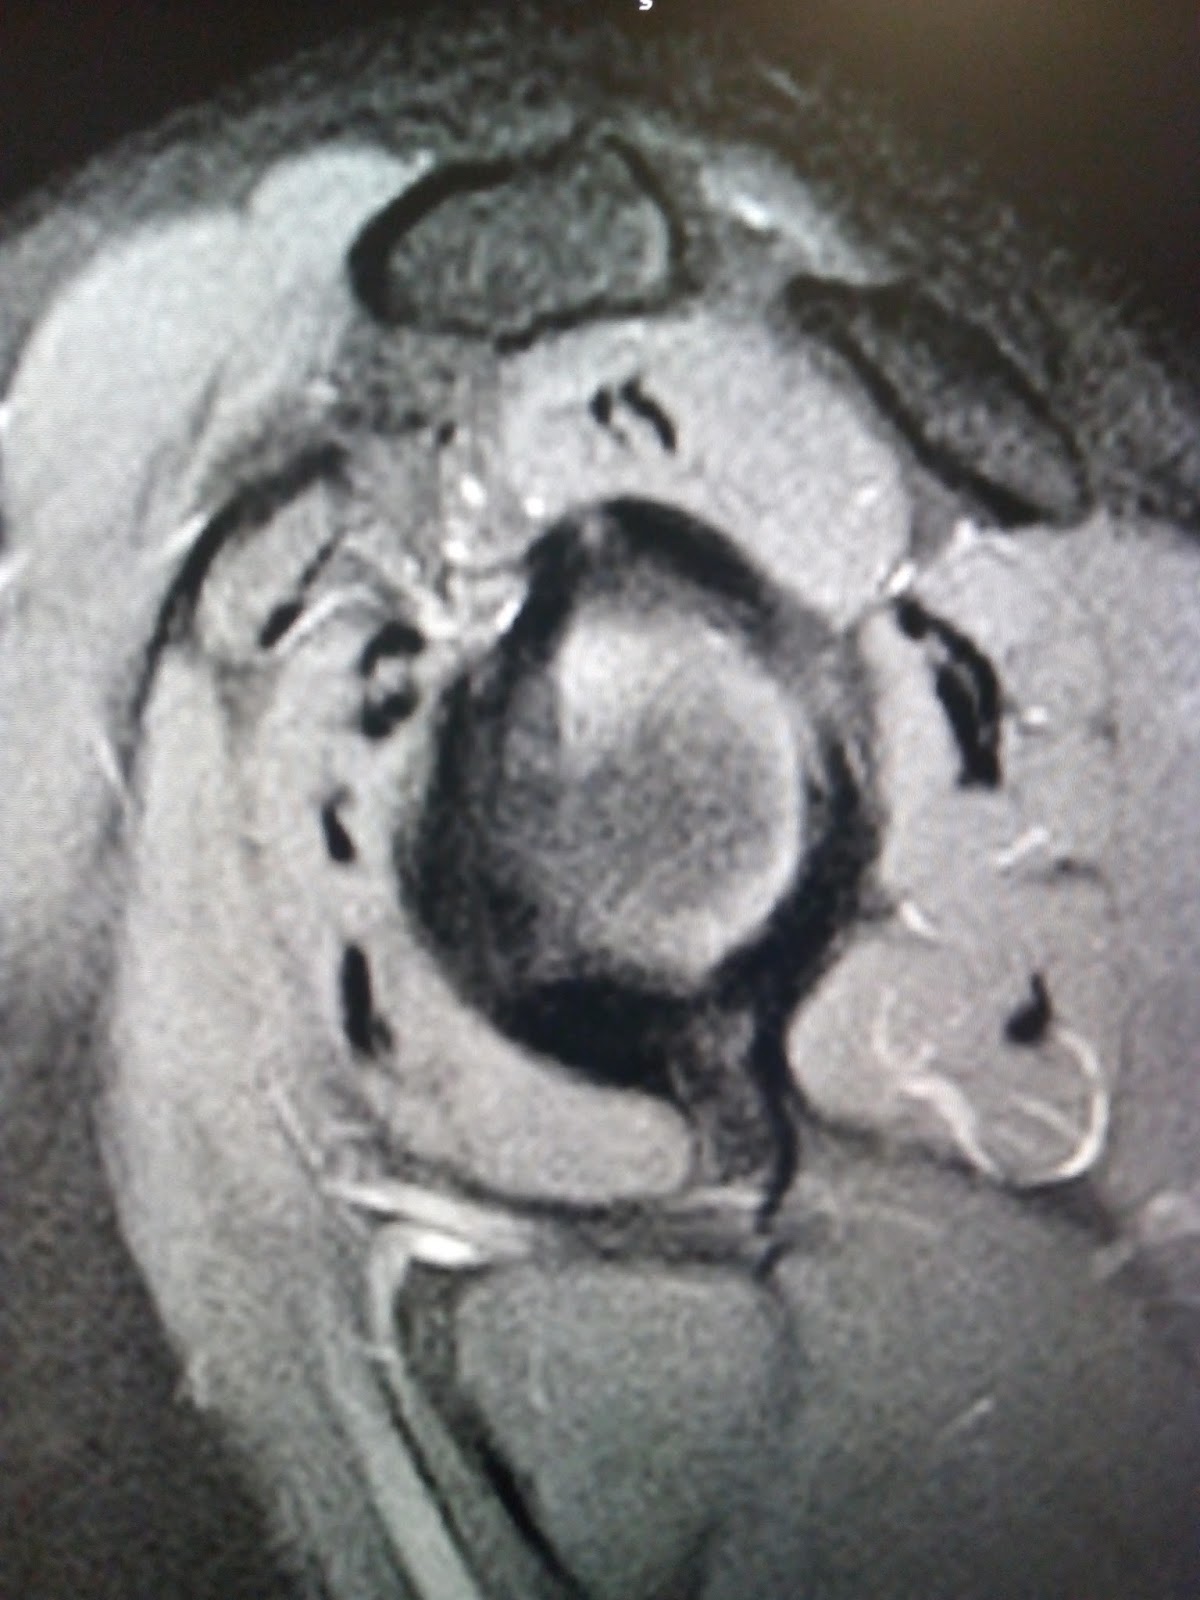

from www.indianradiology.com

Adhesive capsulitisMRI Sumer's Radiology Blog

From sumerdoc.blogspot.com

Adhesive capsulitisMRI Sumer's Radiology Blog Define Adhesive Capsulitis adhesive capsulitis, also known as “frozen shoulder,” is a common shoulder condition characterized by pain and decreased range of motion, especially in external rotation. adhesive capsulitis is a chronic fibrosing condition characterized by insidious and progressive severe restriction of both. frozen shoulder is also referred to as adhesive capsulitis, painful stiff shoulder, and periarthritis. frozen shoulder. Define Adhesive Capsulitis.

Adhesive capsulitisMRI Sumer's Radiology Blog Define Adhesive Capsulitis the hallmark sign of frozen shoulder, also known as adhesive capsulitis, is the inability to move your shoulder—either on your own or with the help of someone. frozen shoulder is also referred to as adhesive capsulitis, painful stiff shoulder, and periarthritis. adhesive capsulitis, also known as “frozen shoulder,” is a common shoulder condition characterized by pain and. Define Adhesive Capsulitis.